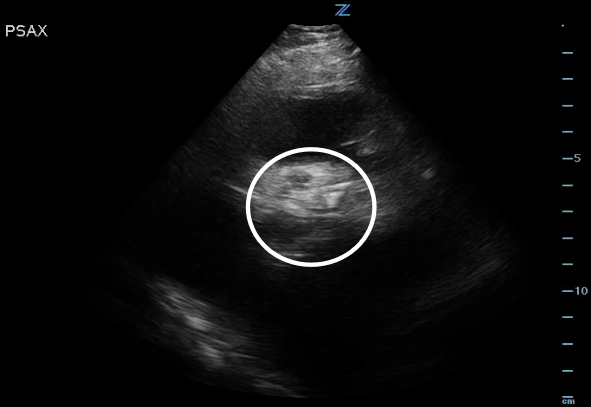

Figure 2. High PSAX (RVOT) view of the AV orifice (circled) closed.

Figure 3. High PSAX (RVOT) view of the AV orifice (circled) open.